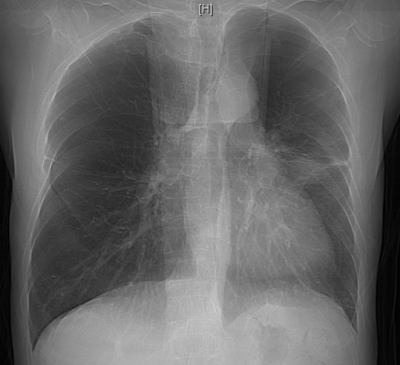

明确诊断后,患者的治疗迎来关键转折点,团队迅速调整方案,启动大剂量糖皮质激素抗炎治疗,治疗效果立竿见影。患者的病情显著改善,氧合指数稳步上升,呼吸困难症状明显缓解。经过精心治疗,他在进入呼吸重症监护室一周后便转入呼吸科普通病房;10天后复查胸部CT,显示肺部弥漫性病变明显吸收好转,顺利出院。后续的定期随访复查也证实其肺部状况持续向好。

双肺病变持续吸收